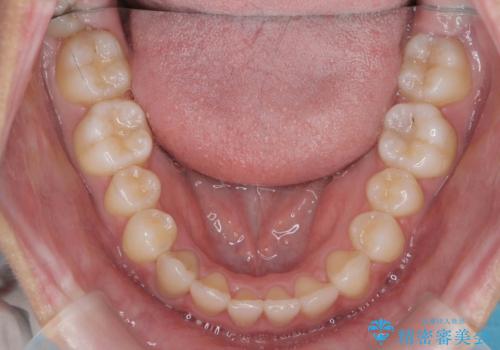

マウスピース矯正で前歯のガタつきを改善

- 上下の前歯のガタつきの改善を求めて、矯正治療を希望され来院されました。

矯正検査の結果、マウスピース矯正システム インビザラインの適応であることからワイヤーを用いず矯正治療を進めることとしました。

1日20時間以上の使用時間をきっちりと守っていただけたため、良好な治療結果、歯並びを手に入れることができました。